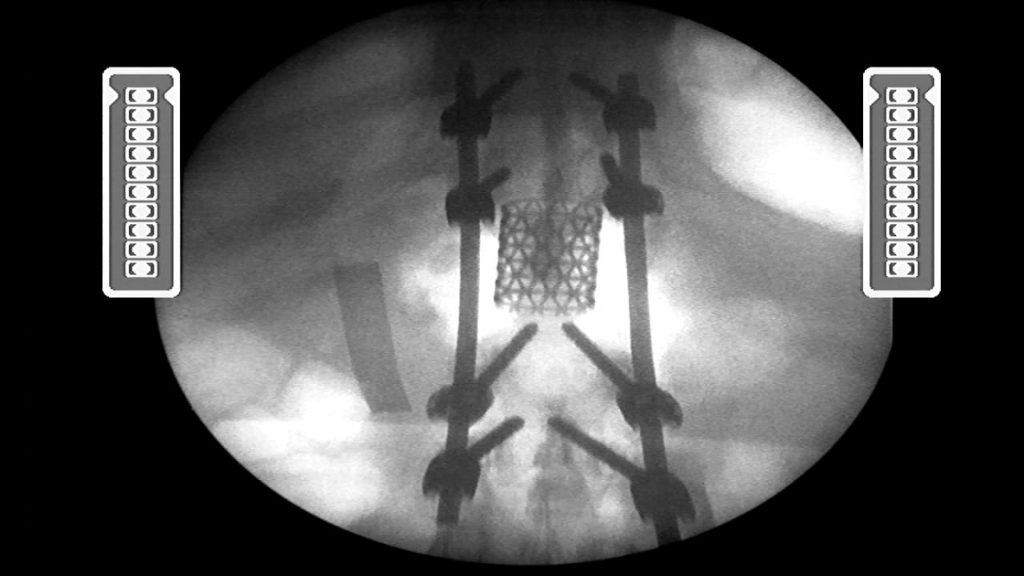

Un paciente que tenía vértebra totalmente dañada fue operado con éxito y le implantaron una prótesis de titanio y barras de fijación.

Esto fue logrado gracias a la pericia de los médicos Leboni Jiménez – cirujano de tórax y cardiovascular, Julián Mosquera – cirujano traumatólogo, dirigidos por el Dr. Paul Méndez Aguilar – Neurocirujano del hospital de Huaraz “Víctor Ramos Guardia”-

“Espondilectomia vía posterior más artrodesis dorsal”, es el nombre de la cirugía realizada a paciente de 55 años de edad, de la provincia de Chacas, quien sufrió un accidente, dañando su columna y  que fuera referido de emergencia el hospital de Huaraz. Ahora se recupera en el servicio de cirugía hospitalización.